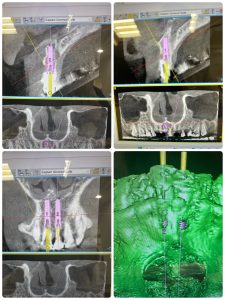

年明けは、左上ソケットリフト2本予定

来週のオペ左右前歯2本、破折に病巣

即時荷重予定、固定を獲得しなければならない、18ミリ予定

今日は午前午後とジルコニア8本セットに根管治療病巣の縮小確認やら楽しみMAX day